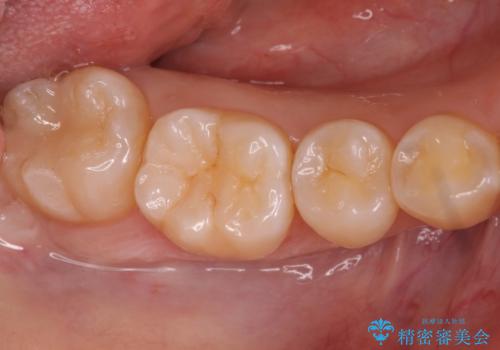

奥歯の深い黒ずみ セラミックインレーでの治療

変色しない材料をご希望されたためセラミックインレーでの治療となりました。

樹脂は変色していきますがセラミックは変色しない材料であるため、長く使いたい方にお勧めです。

- 右下7 セラミックインレー 77,000円費用は治療当時の料金となります